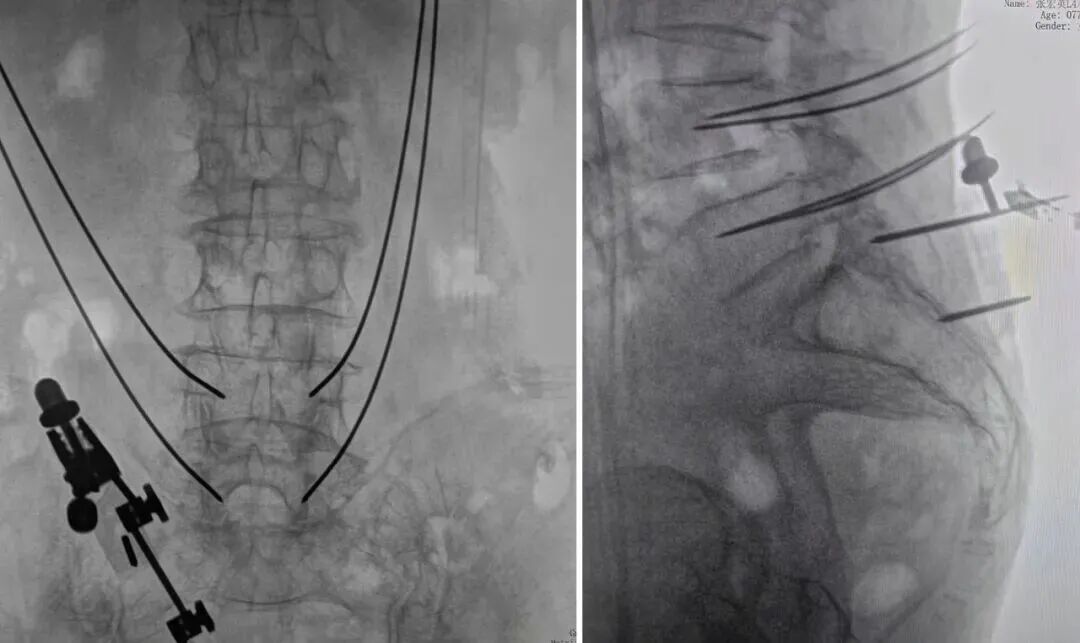

患者:77岁,女性

术前诊断:腰椎管狭窄、腰椎失稳

手术方案:机器人导航下MIS-TLIF手术,先减压再置钉

❑ 机器人辅助定位螺钉植入——精准保障

机械臂抵达规划的穿刺点,导向器对准规划的螺钉植入路径,术者通过导向器分别打入4根定位克氏针。术中验证定位准确,医生完成4枚椎弓根螺钉的植入。与传统徒手置钉相比,机器人辅助可避免因 “手感偏差” 导致的螺钉偏移,提高了置钉的精准度。